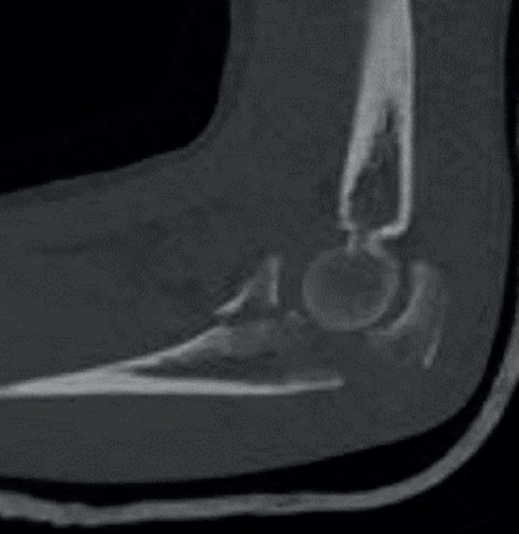

Las fracturas de apófisis coronoides aisladas son raras, generalmente las encontraremos asociadas a roturas ligamentosas o fracturas de otros huesos del codo. Existen 3 patrones de inestabilidad aguda de codo que asocian fracturas de apófisis coronoides con lesiones ligamentosas y óseas específicas. En función de la morfología de la fractura, podremos sospechar esas lesiones con anticipación y planificar la cirugía. Las radiografías simples son insuficientes para objetivar los fragmentos con claridad, pero es la primera prueba diagnóstica que debemos realizar. Comprobaremos si existe luxación o subluxación, y si hay apertura del espacio radiocapitelar o humerocubital que nos alerte de una posible lesión ligamentosa. Una tomografía axial computarizada (TAC) con reconstrucción 3D será imprescindible para visualizar los fragmentos. Una resonancia magnética (RM) nos dará más información sobre las lesiones de las partes blandas.

Regan y Morrey describieron 3 tipos de fracturas de coronoides según el tamaño del fragmento únicamente en el plano sagital. Las de tipo I son fracturas de la punta, las de tipo II las que afectan a menos del 50% de su altura y las de tipo III cuando el fragmento es mayor del 50% (Figura 1). Actualmente se usa la clasificación de O’Driscoll (Tabla 1), que la amplió teniendo en cuenta además la localización y el número de fragmentos (Figura 2)(3,4).